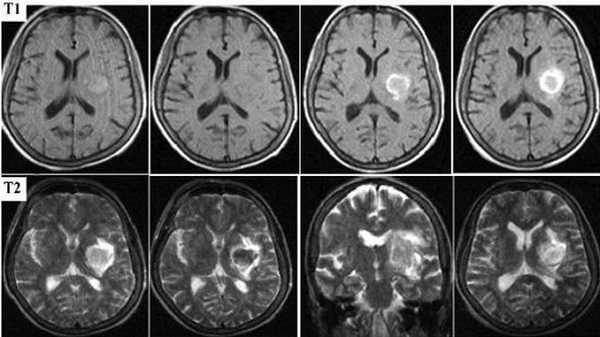

Картина развития ишемического инсульта на МРТ (Т1- и Т2-взвешенные изображения)

Острый период (1-7 день) характеризуется появлением четко ограниченных светлых участков на МРТ в Т2-взвешенном режиме. На Т1 ВИ очаги некроза имеют гипоинтенсивный сигнал.

Головной мозг на МРТ при разных режимах сканирования

Картина МР-сканирования при ОНМК зависит от вида процесса. Различный патогенез приводит к появлению на снимках МРТ дополнительных признаков инсульта. Большей информативностью магнитно-резонансная томография обладает в отношении инфаркта головного мозга, диагностика которого может представлять трудности ввиду отсутствия на ранней стадии выраженной клинической картины.

Для заболевания характерно появление очагов некроза, вызванного нарушением кровоснабжения определенного участка мозга. В острой стадии наблюдается утолщение извилин коры головного мозга, стирается граница между серым и белым веществом. В период восстановления зону инфаркта определяют как участок кистозного или глиозного перерождения.